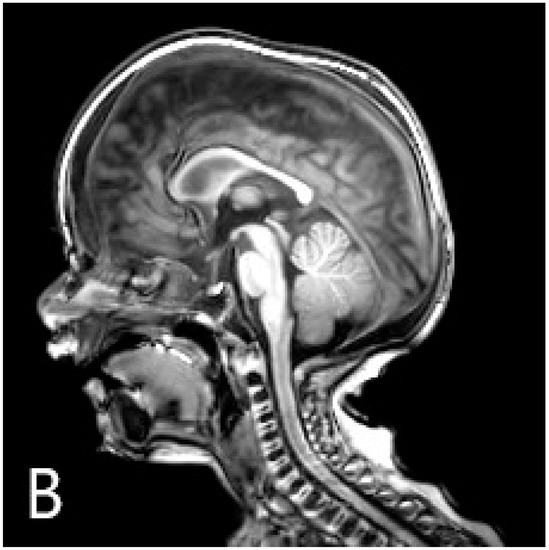

A six-month-old male patient diagnosed with ARO was admitted to our transplantation unit. The patient’s clinical presentation was characteristic of the disease: deformed sclerotic skull, multiple fractures, optic nerve atrophy with progressive visual impairment, and thrombocytopaenia with hepatosplenomegaly as the sign of bone marrow involvement. The auditory system is often affected in ARO, but the patient showed no sign for otologic involvement of the disease at this time. Diagnostic radiography of the chest and cranial MRI can be seen in Figure 1.

Figure 1.

Pre-transplantation radiography (A) shows increased bone density, rachitic malformation in ribs, and endobone appearance in vertebrae and humeri. Sagittal T1-weighted MR image (B) demonstrates the sclerosis of the calvaria. Axial T2-weighted MR image (C) shows optic canal stenosis and optic nerve atrophy.